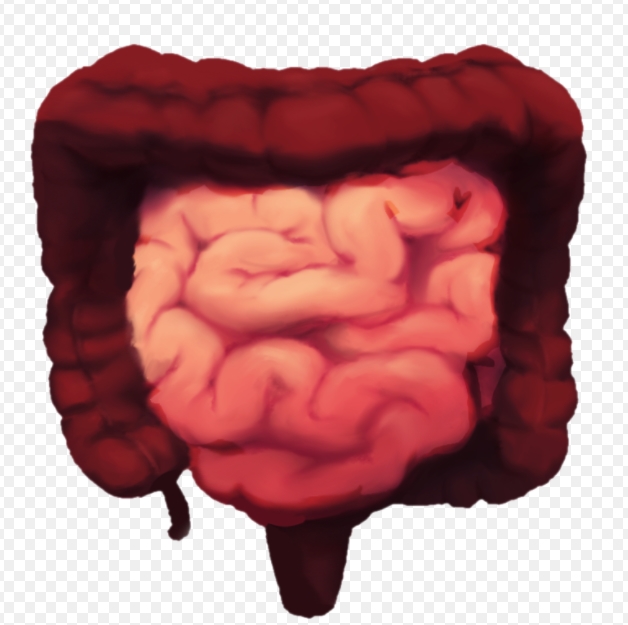

소장이나 대장 일부에서 여러 원인으로 인해 부분적으로나 또는 완전히 장의 일부가 막혀서 장 속에 있던 음식물과 소화액, 가스 등의 내용물이 배 안에서, 장 속에서 축적되면서 장애를 일으키게 됩니다. 이것을 장염전, 장폐색, 장꼬임이라고 합니다. 물론 그 꼬인 부분의 증상 정도에 따라 이름을 달리 부를 수도 있습니다.

장꼬임 생긴 부분에서의 통증으로 시작되어 복부 전체로 통증이 퍼지게 되는데 여기에 가스 등이 차면서 복부팽창, 복부팽만이 발생할 수 있습니다. 그리고 복통에 동반된 구토 등으로 탈수 증상이 생길 수 있습니다.